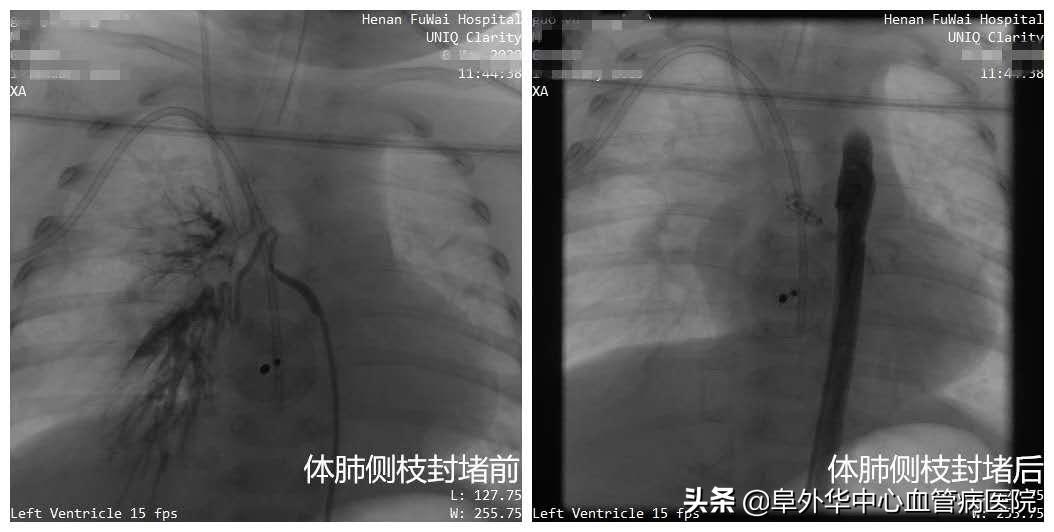

范太兵教授像福尔摩斯一样,大胆推测、抽丝剥茧,逐步逼近事情的真相。进一步掌握证据后,行家们心里有了底。无影灯下,范太兵教授、宋书波博士等行家开始实施手术。在先进的杂交手术室,进行术中动脉造影,打入造影剂后果然发现,小患者有粗大体肺侧枝形成,直径足有4毫米以上!正是这根本来不该存在的血管,导致血液灌注肺部,它才是引起肺炎和气喘的真正元凶,而室间隔缺损(中轻度)和动脉导管未闭不会造成这样的结果。

紧接着,行家们一鼓作气,为孩子实施了“房间隔缺损微创封堵+体肺侧枝封堵术”。整个手术过程,仅有1.5个小时。范太兵教授等行家不但抽丝剥茧找到“真凶”,而且用微创手术代替开胸手术,不但大大降低创伤,而且为患者节省了大量费用。